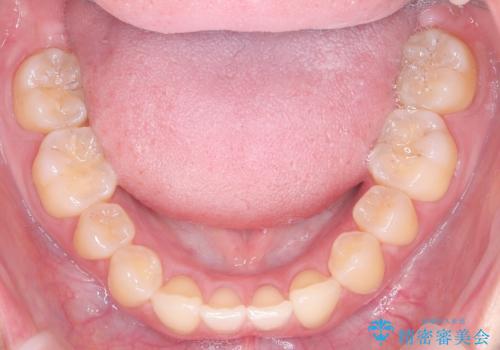

- 患者様は、上下の噛み合わせのバランスが悪く、特に上顎の前歯の突出を気にされて来院されました。診査の結果、下顎の歯並びに合わせて上顎を後方へ移動させる必要があると判断し、上顎の小臼歯2本を抜歯することを提案しました。目立たない矯正を希望されたため、**インビザライン(マウスピース矯正)**を選択。計画的にスペースを作りながら、バランスの取れた歯並びを目指しました。

治療はまず、上顎の小臼歯を2本抜歯し、そのスペースを利用して前歯を後方へ移動させました。インビザラインはアタッチメントを併用し、より効率的に歯を動かせるよう調整。定期的なチェックとアライナーの交換を続け、約3年かけて理想的な歯並びと噛み合わせを実現しました。治療後はリテーナーを使用し、安定した状態を維持。患者様からは「口元がスッキリし、横顔の印象も変わった」と嬉しいお声をいただきました。